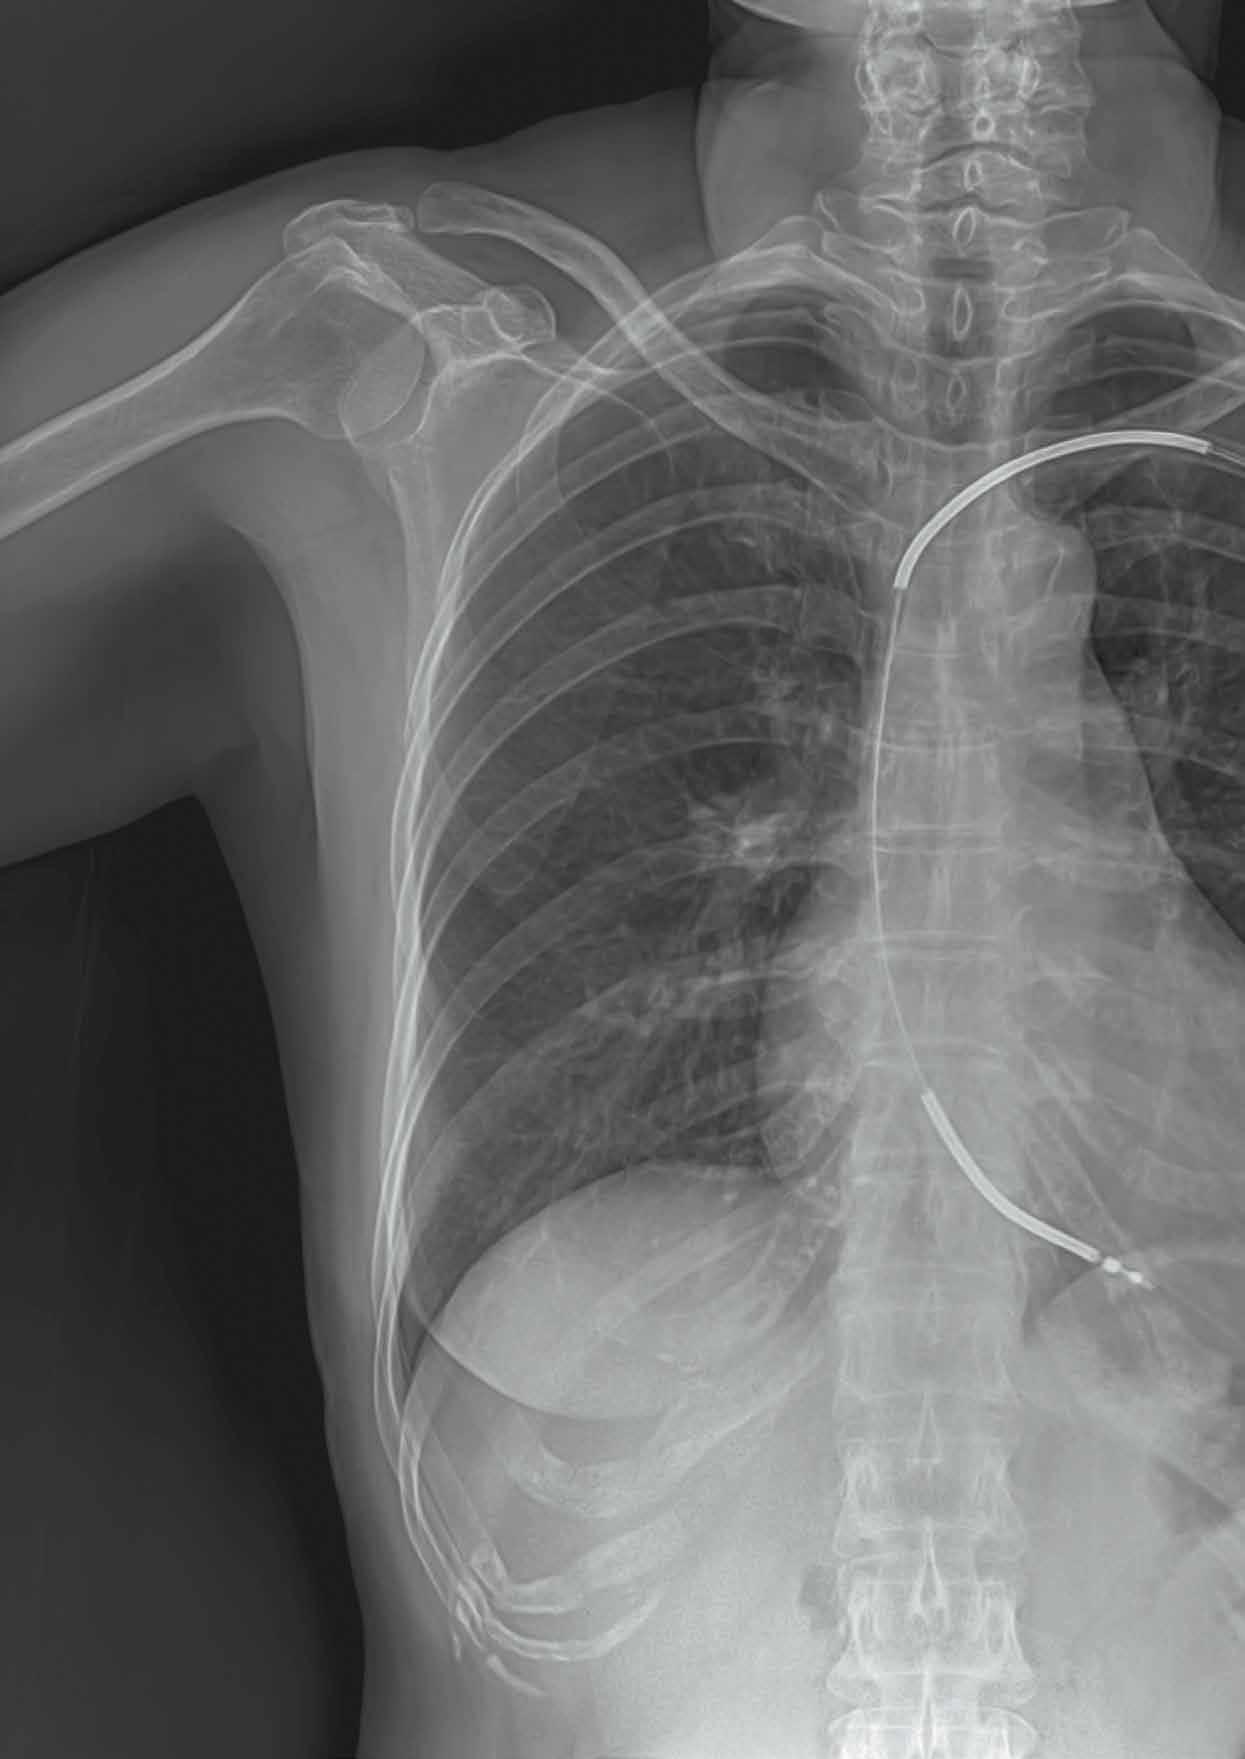

«Auf den Induktionsherd sollte man sich nicht unbedingt legen»

Kann man trotz Herzschrittmacher sterben? Geht an der Sicherheitsschleuse am Flughafen jedes Mal der Alarm los? Kardiologe Pascal Köpfli beantwortet die drängendsten Fragen zu den kleinen Lebensrettern.

Wozu braucht man einen Herzschrittmacher?

Ein Herzschrittmacher sorgt dafür, dass das Herz schnell genug schlägt und keine Pausen macht. Er unterstützt das Herz, um zu verhindern, dass es aufhört zu schlagen.

Welche Arten von Herzschrittmachern gibt es?

Heute können wir das Herz auf verschiedene Arten stimulieren: Der Einkammerschrittmacher hält das Herz mit einer Elektrode in Gang. Der Zweikammerschrittmacher stimmt zusätzlich die Frequenz der Vorhöfe und der Herzkammern aufeinander ab. Den Dreikammerschrittmacher setzen wir insbesondere bei Patienten mit einer Herzschwäche ein, damit der Herzmuskel wieder an Kraft gewinnt und synchroner schlägt. Seit einigen Jahren gibt es ausserdem sogenannte elektrodenlose, intrakardiale Schrittmacher. Sie werden direkt ins Herz eingesetzt, sind rund 14-mal kleiner als herkömmliche Geräte und wiegen weniger als zwei Gramm.

Wie lange dauert der Eingriff, um einen klassischen Herzschrittmacher zu implantieren?

In der Regel dauert eine solche Operation 30 bis 60 Minuten unter Lokalanästhesie. Abhängig vom Alter und von der generellen Konstitution des Patienten, führen wir den Eingriff ambulant oder stationär durch.

Wie viele Schrittmacher implantieren Sie am KSB pro Jahr?

Rechnet man alle Arten von Implantaten in der Kardiologie zusammen, kommen wir auf gegen 200 Eingriffe pro Jahr.

Löse ich mit einem Schrittmacher am Flughafen einen Alarm aus?

Modelle mit einem höheren Metallanteil lösen eher einen Alarm aus. Deshalb erhält jeder Patient einen Ausweis. Dieser kann bei Sicherheitskontrollen vorgezeigt werden und ist auch bei medizinischen Notfällen von grosser Hilfe.

Welche Fragen treiben Ihre Patienten um?

Ich werde immer wieder gefragt, ob man mit einem Herzschrittmacher sterben kann. Man kann. Denn wenn andere Organe versagen, hilft auch ein künstlich schlagendes Herz nicht mehr. Andere Patienten möchten wissen, ob sie mit dem Implantat an ihrem Induktionsherd kochen können. Wenn sie ihn normal verwenden und sich nicht direkt auf die Herdplatte legen, ist das kein Problem. Vorsicht ist bei grösseren Magnetfeldern geboten: Vor und nach einer MRI-Untersuchung zum Beispiel müssen wir den Schrittmacher neu einstellen. Gewisse industrielle Arbeiten mit starken Magnetfeldern, wie etwa mit Bogenschweissgeräten, sind mit einem Herzschrittmacher nicht mehr möglich.

Haben Sie einen Fall in Erinnerung, der Sie besonders berührt hat?

Ich erinnere mich sehr gerne an ein Ehepaar, das immer Arm in Arm in die Sprechstunde kam – in der freien Hand jeweils einen Gehstock. Beide waren weit über 90, beide hatten einen Herzschrittmacher und ihre Beziehung war beinahe symbiotisch. Mittlerweile sind die beiden gestorben; aber sie lebten sprichwörtlich im Takt miteinander. Für mich ist es das Schönste, meinen Patienten mit einem Schrittmacher ein Stück Lebensqualität zurückzugeben.

Lesen Sie im Blog, warum Frauen- und Männerherzen unterschiedlich auf Stress reagieren.

Pascal Köpfli ist Leitender Arzt und Stv. Leiter Kardiologie am KSB.